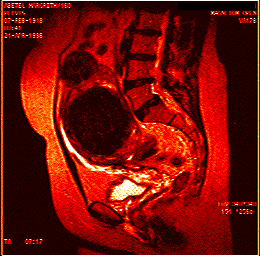

Musculosketal cases

Head and neck cases

Spine cases

Abdominal cases

Soft parts